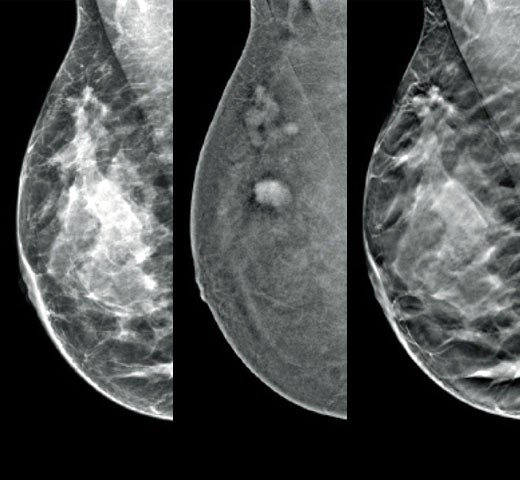

Het is bekend dat een hogere borstdichtheid het risico van een vrouw op borstkanker vergroot.1 De behoefte aan nauwkeurige, objectieve analyses is daarom cruciaal. Aangedreven door machine learning analyseert Quantra-technologiesoftware zowel 2D™- als tomosynthesebeelden op verdeling en textuur van parenchymweefsel. Het deelt borsten in vier categorieën voor borstsamenstelling in, in overeenstemming met de richtlijnen van de American College of Radiology (ACR) BI-RADS Atlas 5e editie.2

Naast volume spelen het patroon en de textuur van fibroglandulair weefsel mogelijk net zo'n belangrijke rol bij de mammografische voorspelling van kankerrisico.3-5 Door de textuur en het patroon van de borst te analyseren en te categoriseren, kan onze technologie de nauwkeurige informatie leveren die u nodig hebt om consistentere en betrouwbaardere scorebepaling te verkrijgen en zelfverzekerd patiëntspecifieke screening te ontwerpen.

Objectief machine-learningalgoritme dat de borstdichtheidscategorie toewijst op basis van analyse van de textuur en patronen van het borstweefsel.